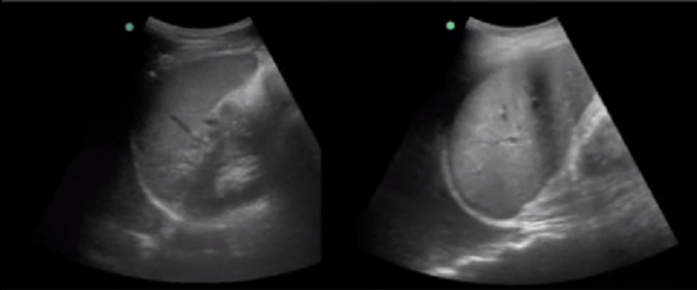

RUSH Pleural/Abdominal Fluid Yes/No Comparison Image